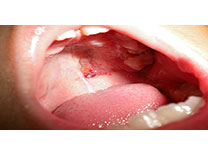

口腔溃疡

口腔溃疡是指口腔黏膜发生炎性水肿、溃烂,有烧灼痛。口腔溃疡与免疫关系密切。其次是与某些疾病有关如胃、十二指肠溃疡、结肠炎、偏食、消化不良、腹泻等;一些生活习惯如…【详细】